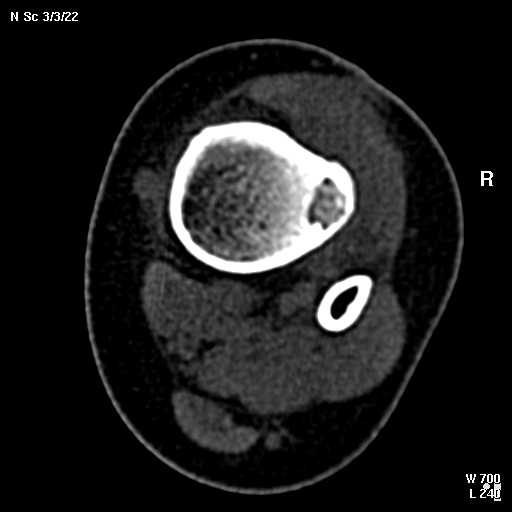

В обсуждении темы возникла необходимость дополнительных данных.

КТ изображения передаю на мой взгляд самые демонстративные. Их любезно записал коллега,

проводивший исследование в другом городе.

Прошу прощения за немного некоректную отправку КТ-снимков но по другому не получается :)

с уважением Николай Петрович.